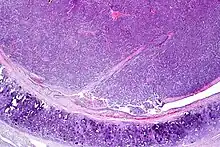

| Atypical pulmonary carcinoid. H&E stain. | |

Atypical carcinoid tumors have increased mitotic activity (2-10 per 10 HPF), nuclear pleomorphism or foci of necrosis.

Atypical carcinoid of the lung exhibiting endobronchial growth, increased mitotic activity was seen (2-10 per 10 HPF). H&E stain.